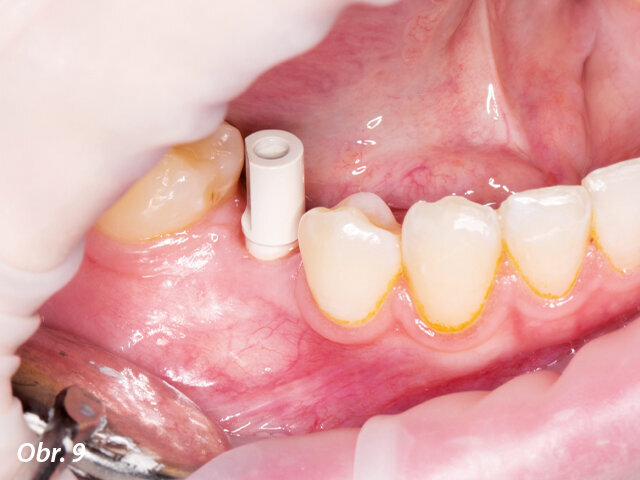

Za účelem navržení náhrady byl na implantát umístěn skenovací abutment.

Po třech měsících byl na implantát umístěn skenovací abutment a zhotoven intraorální sken situace přístrojem Planmeca Emerald za účelem navržení korunkové náhrady.